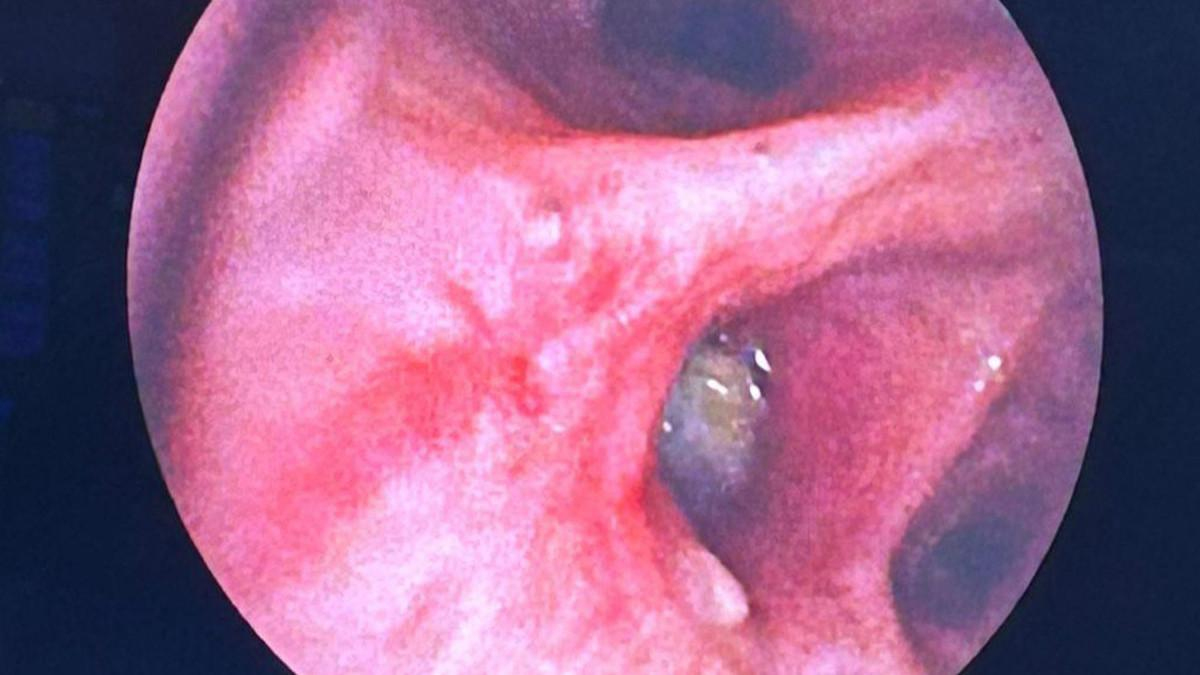

Doç. Erhan Uğurlu’nun muayene ettiği Yurteri’nin hava resimlerini görüntülemek için yapılan fiberoptik bronkoskopi işlemi sırasında beklenmeyen görüntüyle karşılaşıldı.

hastaların sağ taramalarında, bulunduğu hava yolunu kapatan hücreler tanesi farklı bulundu.

Yurteri’nin taramalarındaki tahıl parçalarını ameliyatla çıkarın.

Aspirasyon denilen cüruf yabancı cisimlerin kaçmasının genellikle çocuklarda beklense de düşük boyutlarda de görülebiliyor. Bezelye tanesi olması nedeniyle hava yolunda küçük bir tıkanıklığa yol açan hastalarda bulgu veren yabancı cisim aspirasyonlarının kül, balgam, hırıltı gibi yakınmalara, zatürre, akciğerde sönme gibi yuvalara da yol açabilir. Hem KOAH’a yönelik bronkoskopik volüm küçültme bobin noktasında hem de taramaya kaçan ampul taneleri alacağı hasta, sonrasında izleminde sorun görülmedi. Hastayı kontrollerine gitmek üzere taburcu ettik.